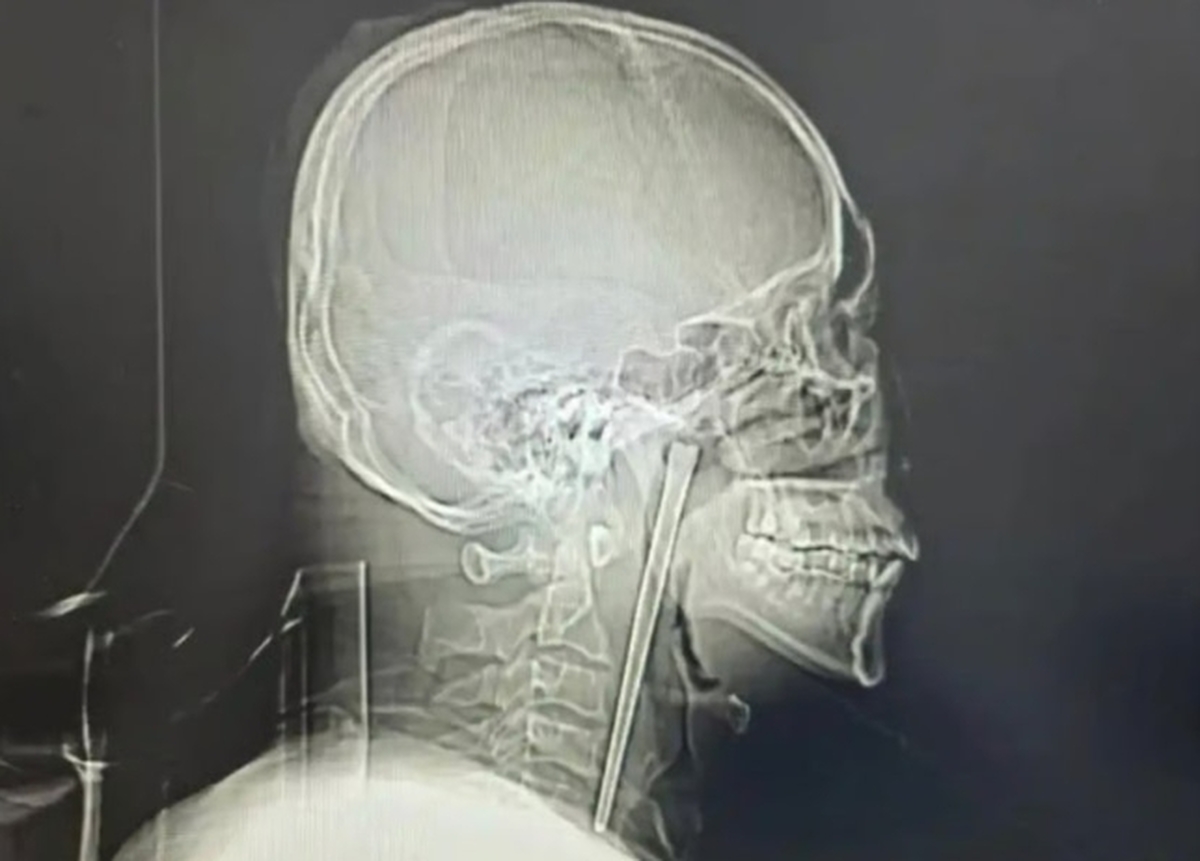

정밀 검사를 통해 왕씨가 삼킨 금속 젓가락이 목 안쪽 연구개 부위에 박혀 있음이 확인됐다.

의료진은 다행히 주변 점막 손상이 없고 성대 기능도 정상 상태를 유지하고 있다고 설명했다. 의료진은 목 절개를 원하지 않는 환자의 의견을 수용해 구강을 통한 최소침습 수술을 실시했으며, 12㎝ 길이의 젓가락 제거에 성공했다.